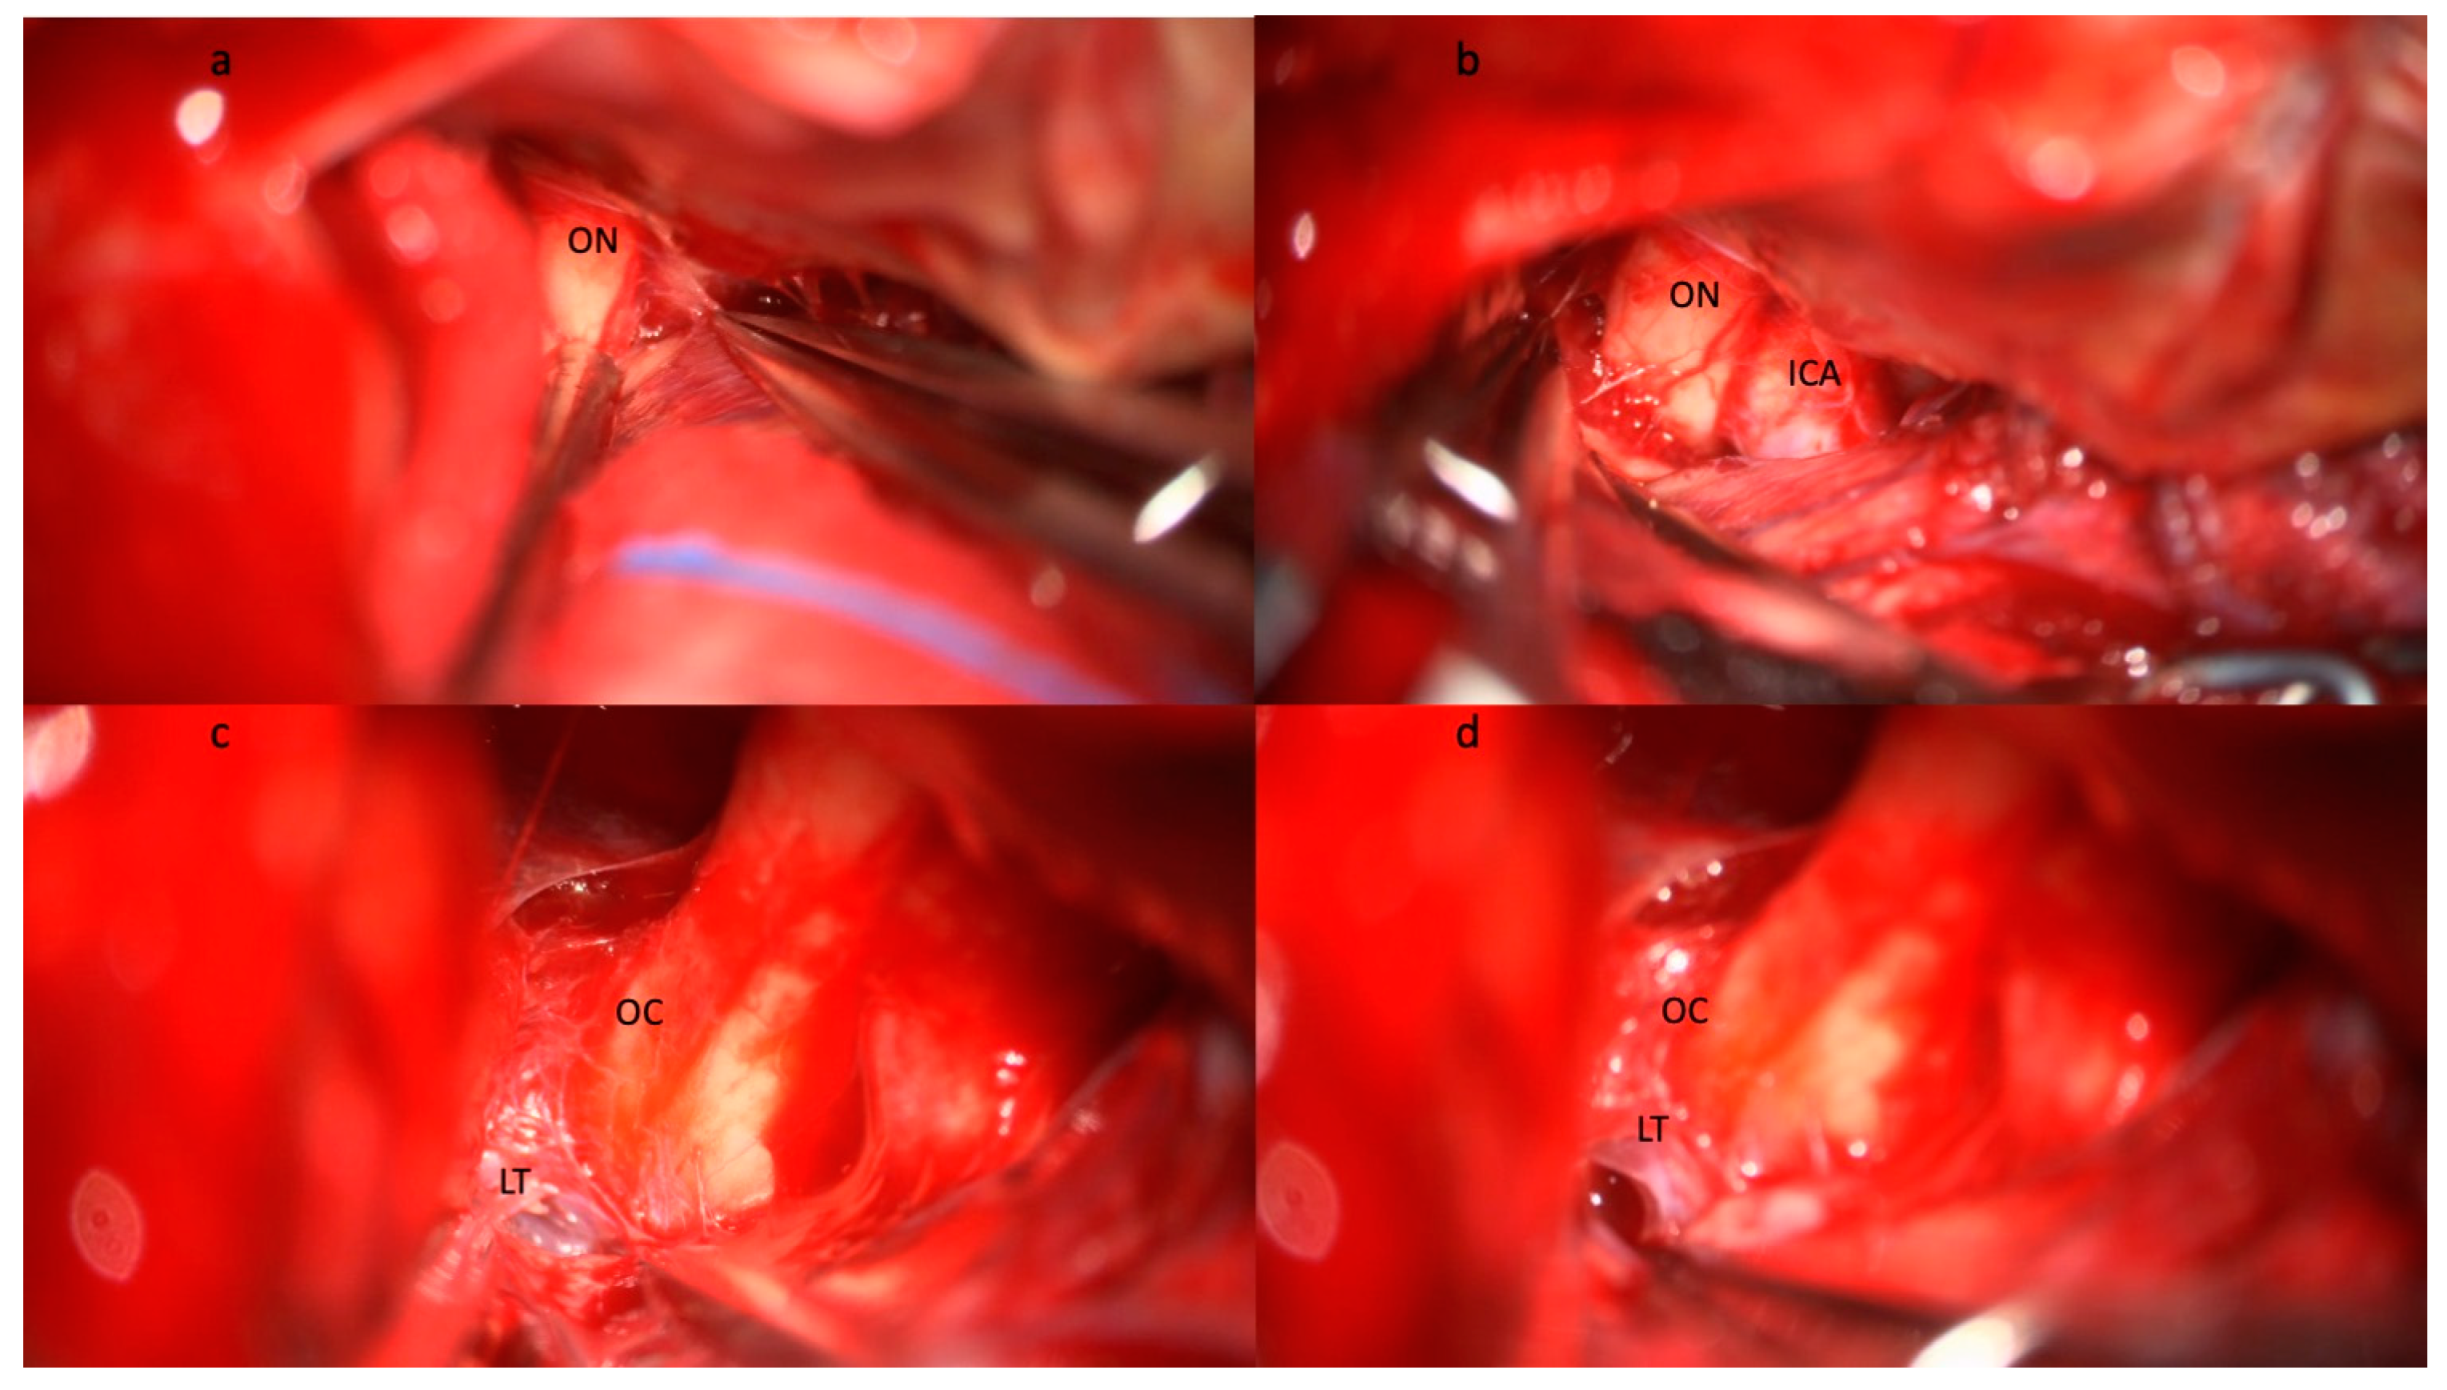

- Giammattei, L.; Starnoni, D.; Messerer, M.; Daniel, R.T. Basal Cisternostomy for Severe TBI: Surgical Technique and Cadaveric Dissection. Front. Surg. 2022, 9, 915818. [Google Scholar] [CrossRef]

- Sturiale, C.L.; Ricciardi, L.; Marchese, E.; Puca, A.; Olivi, A.; Albanese, A. Surgical Treatment of Anterior Communicating Artery Aneurysms: Hints and Precautions for Young Cerebrovascular Surgeons. J. Neurol. Surg. A Cent. Eur. Neurosurg. 2020, 81, 463–471. [Google Scholar] [CrossRef] [PubMed]

- Sturiale, C.L.; Rapisarda, A.; Marchese, E.; Puca, A.; Olivi, A.; Albanese, A. Surgical Treatment of Middle Cerebral Artery Aneurysms: Hints and Precautions for Young Cerebrovascular Surgeons. J. Neurol. Surg. A Cent. Eur. Neurosurg. 2021, 83, 75–84. [Google Scholar] [CrossRef] [PubMed]